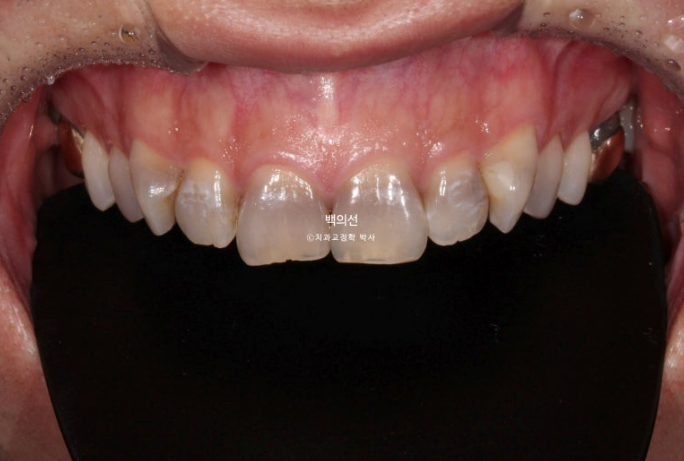

In the lower front teeth, there are varying heights in addition to the canine crowding.

The lower front teeth have stricter conditions for no-prep laminate than the upper front teeth.

Because the laminate has to wrap around the incisal edge of the lower front teeth, there needs to be some distance between the upper front teeth and the lower front teeth.

The canine crowding is fairly severe.